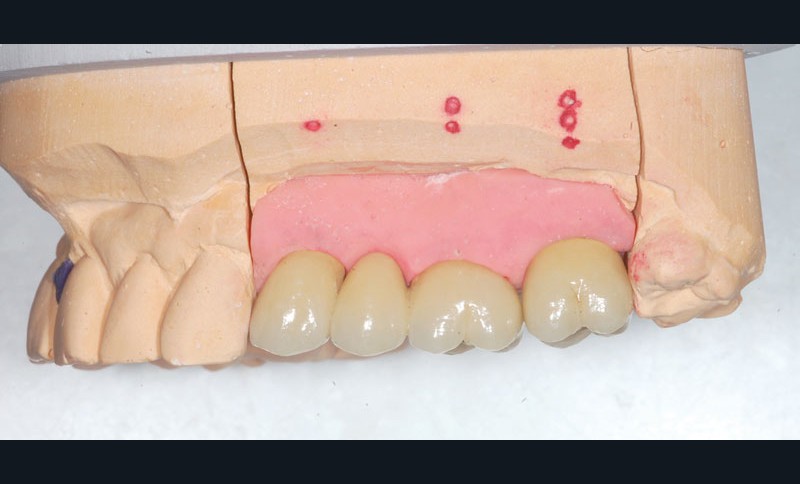

Le bridge 24-26 céramométallique et la couronne unitaire sur 27 sont réalisés. Les piliers CFAO sont transvissés sur les implants, puis les éléments céramo-métalliques sont posés. Le résultat montre un parfait respect du projet prothétique en fonction de la courbe occlusale obtenue avec le bridge transitoire réalisé avec le ProtempTM 4 et une adaptation parfaite.